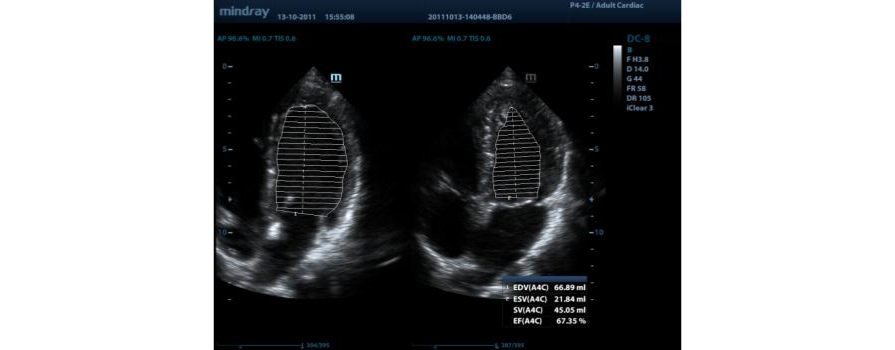

Fracción de eyección automática (AutoEF)

Una forma inteligente de analizar las 2D para reconocer automáticamente los niveles diastólicos/sistólicos y generar la estimación diastólica, el volumen diastólico, la fracción de eyección (EDV/ESV/EF), etc. resultantes del método Simpson.